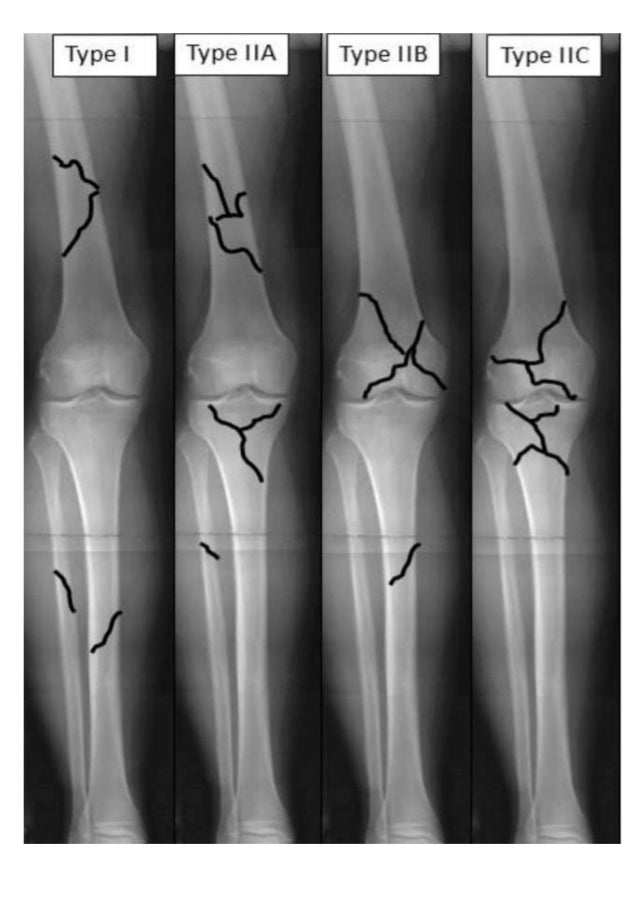

Fraser Classification Floating Knee Pdf . Type ii, articular surface involved; The traumatic floating knee in adults (fk) is a combined injury of the lower limb defined by ipsilateral fractures of the tibia and femur. Three forms of floating knee injuries are distinguished by the fraser classification, which was first presented by fraser et al. This work aims to design a modified fraser's classification and report the clinical outcomes of a series of 28 floating knees. Fraser's classification of floating knee. The floating knees were classified as three types: This is a retrospective study of 30 cases of floating knee classified according to fraser classification, open injuries are classified according to gustilo. Historical evolution of management of femoral fractures in polytrauma patients.